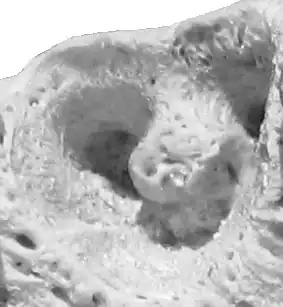

![]() Alvéolo del segundo premolar superior en un hueso maxilar de bovino. | ||

Los alvéolos dentarios, o alveolos dentarios, son las divisiones en compartimentos que presenta el hueso alveolar donde van insertados los dientes, separados entre sí por un tabique interalveolar óseo.

El alvéolo presenta tres regiones, la de las placas corticales, la esponjosa y la alveolar propiamente dicha.

Las placas corticales se disponen en sentido lingual y labial, formando una repisa de sostén muy resistente de hueso compacto, revestida por hueso poroso, que constituye la capa esponjosa. Esta rodea a una capa delgada de hueso compacto, el hueso alveolar propiamente dicho, cuya morfología es reflejo de la forma de la raíz suspendida en su interior.